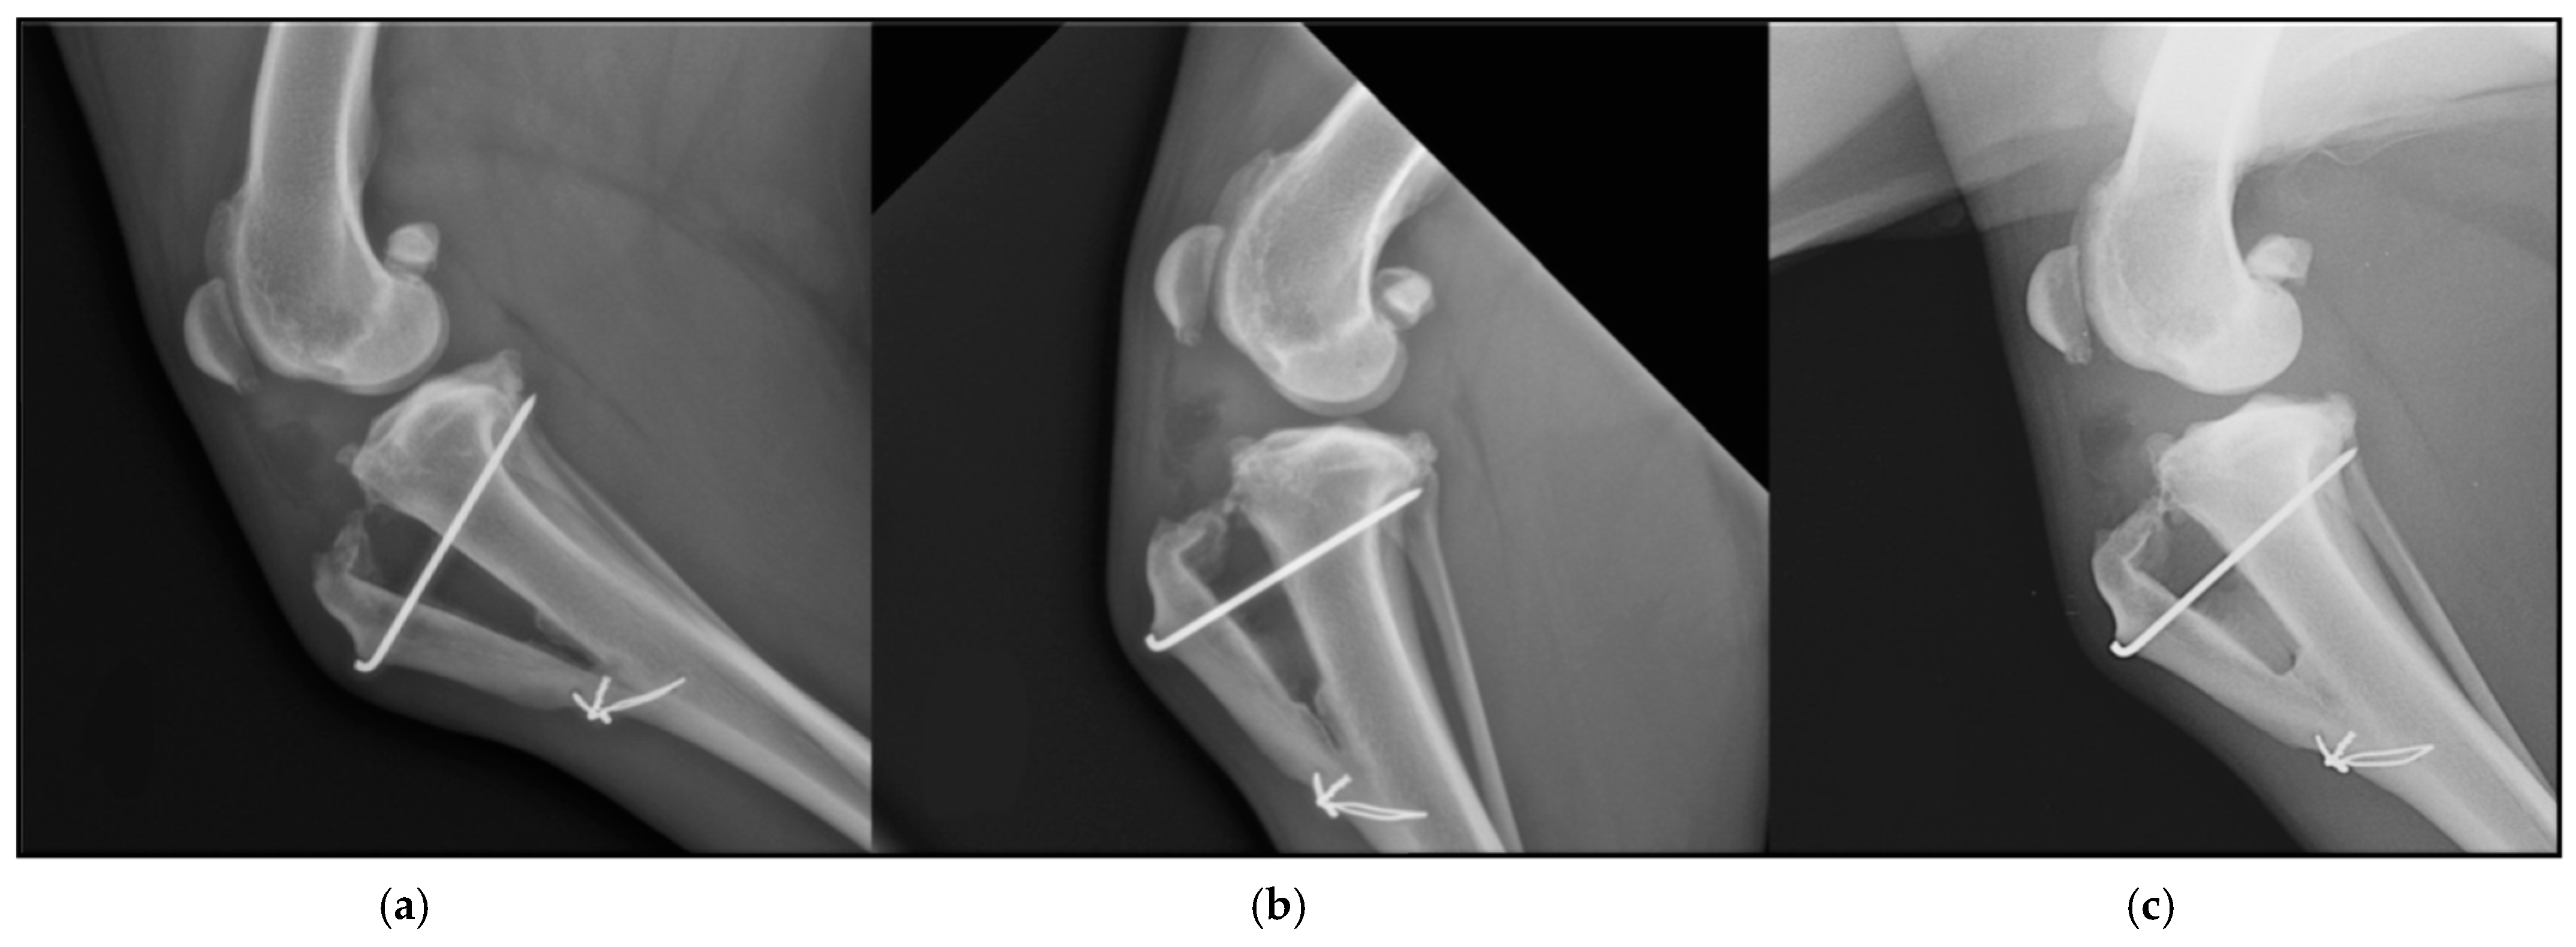

2.2.4. Radiographic Assessment

- Etchepareborde, S.; Brunel, L.; Bollen, G.; Balligand, M. Preliminary experience of a modified maquet technique for repair of cranial cruciate ligament rupture in dogs. Vet. Comp. Orthop. Traumatol. 2011, 24, 223–227. [Google Scholar] [CrossRef]

- Brunel, L.; Etchepareborde, S.; Barthélémy, N.; Farnir, F.; Balligand, M. Mechanical testing of a new osteotomy design for tibial tuberosity advancement using the Modified Maquet Technique. Vet. Comp. Orthop. Traumatol. 2013, 26, 47–53. [Google Scholar] [CrossRef] [PubMed]

- Ness, M.G. The Modified Maquet Procedure (MMP) in Dogs: Technical Development and Initial Clinical Experience. J. Am. Anim. Hosp. Assoc. 2016, 52, 242–250. [Google Scholar] [CrossRef]